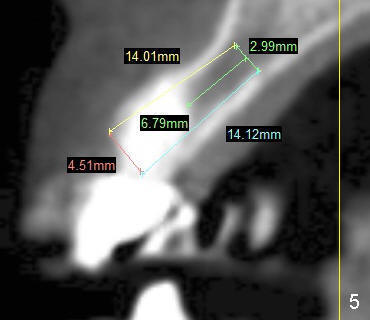

Coronal section shows the height of the alveolus is 21.05 mm (Fig.3); the widths are 7.66 mm and 5.65 mm at the crest and the narrowest area, respectively.

Which of Tatum tapered implants is the most appropriate, 4x17 mm (Fig.4), 4.5x14 (Fig.5) or 5x11 (Fig.6)?